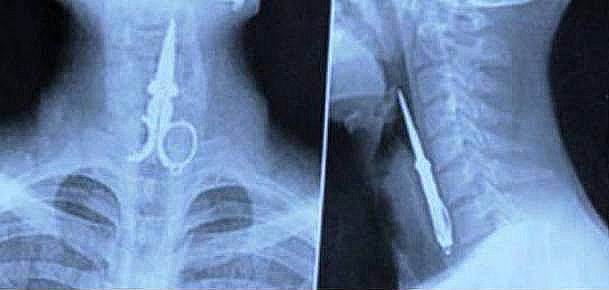

Small scissors

A Chinese man was picking his teeth with a pair of small scissors and accidentally swallowed them when laughing at a joke. This sounds like a horrible joke to us.